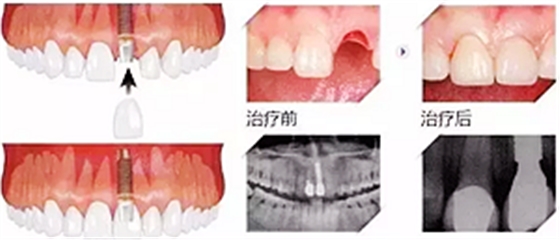

7、大幾千甚至過萬的種植牙

當(dāng)牙齒最終齲壞到只剩殘根,只能拔除,拔牙雖然不貴,但是拔牙之后的鑲牙并不便宜,目前比較好的鑲牙方式種植牙,一般要大幾千甚至過萬元一顆。這個價格對于普通人來說算很貴了。但沒辦法,誰叫你一拖再拖呢,快趁有人工補救的機會種上吧,有些人想種牙還受身體條件限制種不了呢。

那你要說如果壞牙直接拔掉,不鑲牙不就好了?那我只能說No zuo No die!時間久了,兩邊的牙向缺牙的地方倒了,對應(yīng)的咬合面上的牙齒伸長了,這時候會發(fā)現(xiàn)缺牙附近前后左右的牙吃東西都塞牙,長期的塞牙造成其他牙齒的齲壞,開始了上述的循環(huán)。